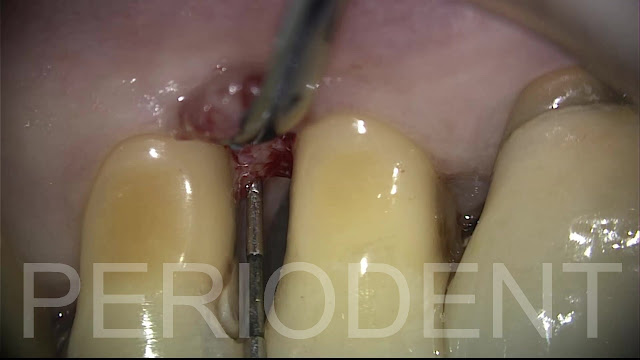

在顯微鏡下進行牙冠加長術